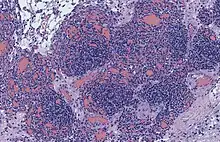

| Micrograph of a kaposiform hemangioendothelioma with "glomeruloid" nodules of endothelial cells. | |

- Kaposiform hemangioendothelioma (also known as "Infantile kaposiform hemangioendothelioma"[3]) is an uncommon vascular tumor, first described by Niedt, Greco, et al. (Hemangioma with Kaposi's sarcoma-like features: report of two cases.(Niedt GW, Greco MA, Wieczorek R, Blanc WA, Knowles DM 2nd. that affects infants and young children, with rare cases having also been reported in adults. Pediatr Pathol. 1989;9(5):567-75.)[2]: 596 [3]: 1782